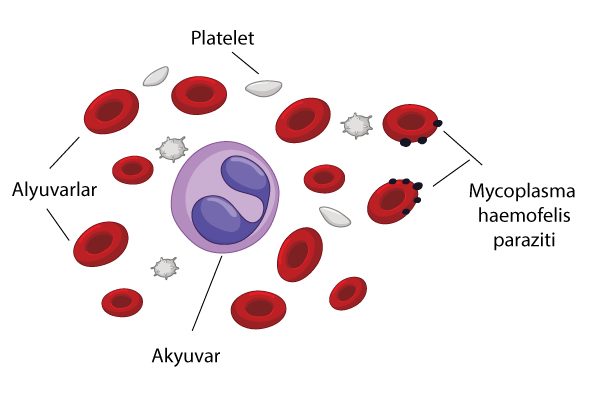

İleri #yaşlı #kedi hastalarda gördüğümüz en yaygın kronik hastalıktır. #Böbreklerde yetmezlik başlandığında takip edilmesi gereken bir sürü parametre vardır sizlere mümkün olduğunca özet bir şekilde bunlardan bahsedeceğim. #Renal #hipertansiyon, böbreğin yetmezliğe girmesine bağlı vücudun verdiği yanıttır, mutlaka yönetilmeli. Diyet çok önemli tuz kısıtlaması, fosfor kısıtlaması ve duruma göre düşük ama yüksek kalitede protein; özetle…